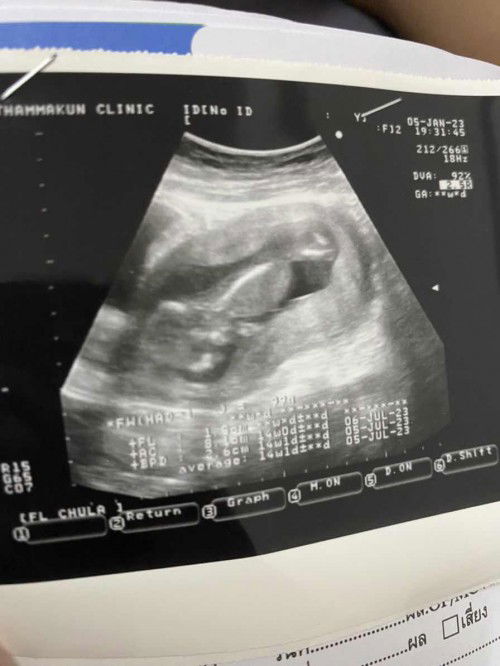

ขอสอบถามแม่ๆค่ะ เราท้องได้ 14 สัปดาห์ ลูกเรากลับหัวหรือหัวต่ำเกินไปมั้ยคะ มันจะเป็นอะไรมั้ยเรามัวตื่นเต้นเลยลืมถามคัณหมอ #แต่คุณหมอบอกน้องโตเร็วมาก หรือไม่ได้พูดอะไรในเชิงที่ว่าจะอันตราย แต่เเม่เครียดนิดหน่อยค่ะท้องแรก